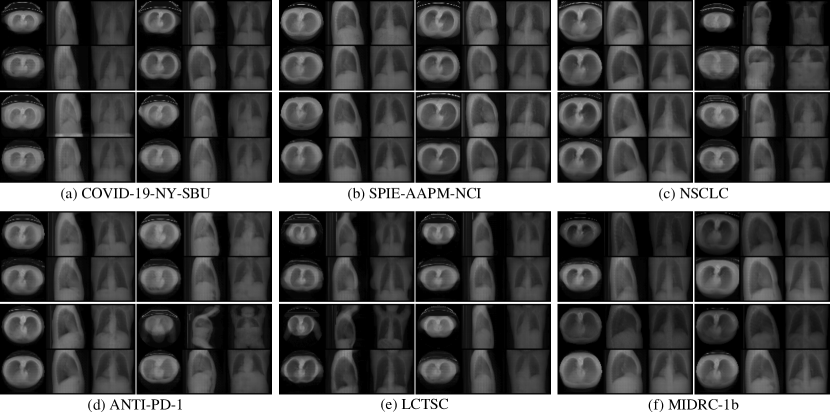

Refer to caption

Figure 5: CT projections from generated 3D volumes on various out-of-distribution lung datasets. Model weights were selected from iteration 5,000 on the LIDC-IDRI dataset [1]. GT projections are displayed in odd rows, while our model’s outputs are shown in even rows.